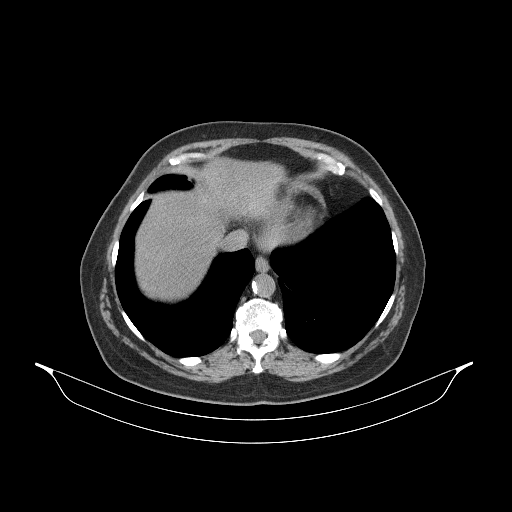

Original VENOUS CT scan

Full window (WL 1023.5, WW 4095 β†’ Low βˆ’1024, High +3071)

Actual HU range: [-160.0, 240.0]

Lung window (WL -600, WW 1500 β†’ Low βˆ’1350, High +150)

Actual HU range: [-160.0, 150.0]

Mediastinum window (WL 40, WW 400 β†’ Low βˆ’160, High +240)